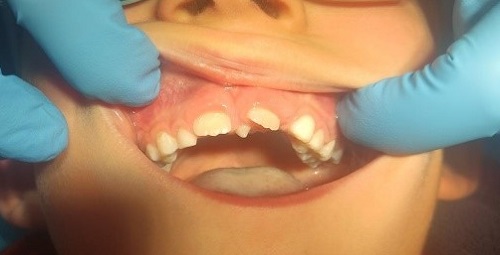

Paciente varón de 10 años, sin antecedentes familiares ni personales de interés, que acude a la consulta de Pediatría por notar un “bulto” en línea media de maxilar superior, por lo que se deriva a la consulta de Odontología. En la exploración dental se observa la presencia de toda la dentición permanente en normoclusión, desgaste selectivo en incisivos inferiores que afecta más a la pieza 32, rotación mesial de la corona del 21 y caries en cara oclusal de 46 (Fig. 4). Se le solicitó una ortopantomografía para valorar el estado de los incisivos. En la radiografía (Fig. 5) vimos la presencia de un mesiodens en la línea media, único, tuberculado y con curvatura apical. El ápice del supernumerario se encuentra próximo al ápice del 21 y altera la correcta alineación de los incisivos inferiores, por lo que presenta desgaste selectivo por oclusión con dicho supernumerario. Además, se aprecia rotación mesial de 21 por la relación con supernumerario y desviación a distal del ápice del 21. Para evitar el daño de incisivos inferiores por prematuridad en oclusión con dicho supernumerario y alteraciones en la posición del 21, se informa a los padres de la necesidad de extraer dicho diente y se realiza en la consulta con anestesia tópica inicial y posterior infiltrativa (Fig. 6).

| Figura 4. Paciente con mesiodens en línea media interincisal, posición vertical, localización palatina a 2 cm de la cara palatina de incisivos centrales superiores |